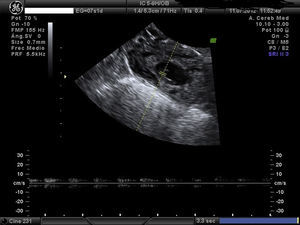

Embarazo actual de 7 semanas de amenorrea con sospecha de embarazo ectópico (EE) cornual. A la exploración, la paciente se encuentra estable, abdomen blando y depresible, sin signos de irritación peritoneal. Hemograma y bioquímica y coagulación normal y la β-HCG de 32.500mU/ml. Se confirma el diagnóstico de EE cornual derecho no accidentado por ecografía, presentando saco gestacional a nivel de cuerno derecho de 13mm con embrión de CRL 1,5mm y actividad cardíaca positiva (figs. 1 y 2). A la izquierda del saco, formación ecogénica mal delimitada de 18×18mm, muy vascularizada, compatible con trofoblasto (fig. 3). Anejos normales y no líquido libre.